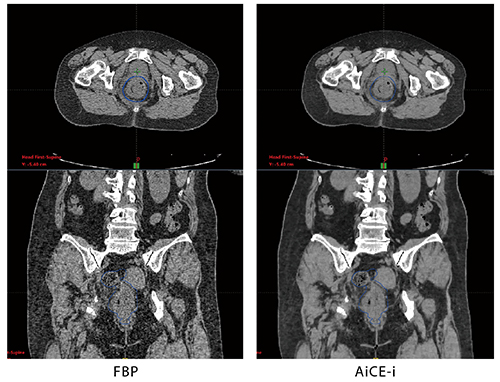

症例2 直腸がん

AiCE-iでは粒状性を維持しながら高いノイズ低減効果が得られている。コンツーリングの精度、効率が向上するとともに被ばく低減も期待される。

現在、治療計画用のCT画像はすべてFBP法で再構成されているが、治療計画への適用を含めたAiCE-iへの期待について芝田主任は、「画質の向上と被ばく低減が可能になることが期待できます。ただ、CT値の変化が起こることが想定されるため、実際の治療計画への適用については品質管理室とも相談しながら進めたいと考えています」と述べる。岡本室長は、「放射線治療のCT値は照射線量を決める重要な情報です。再構成法が変わることで、どのような変化があるのか、今後精密な評価が必要だと考えています。われわれとしてはFBPやAIDR 3Dを含めて安全重視でしっかりと検証を進めて、その結果を発信できればと考えています」と述べる。被ばくの低減について勝田副部長は、「治療計画CTだけを考えれば撮影回数は多くありませんが、IGRT(画像誘導放射線治療)が増加する中で今後は放射線治療全体として被ばくを考慮することは当然求められることです。その中でAiCE-iのような技術の利用は重要で、期待しています」と述べる。